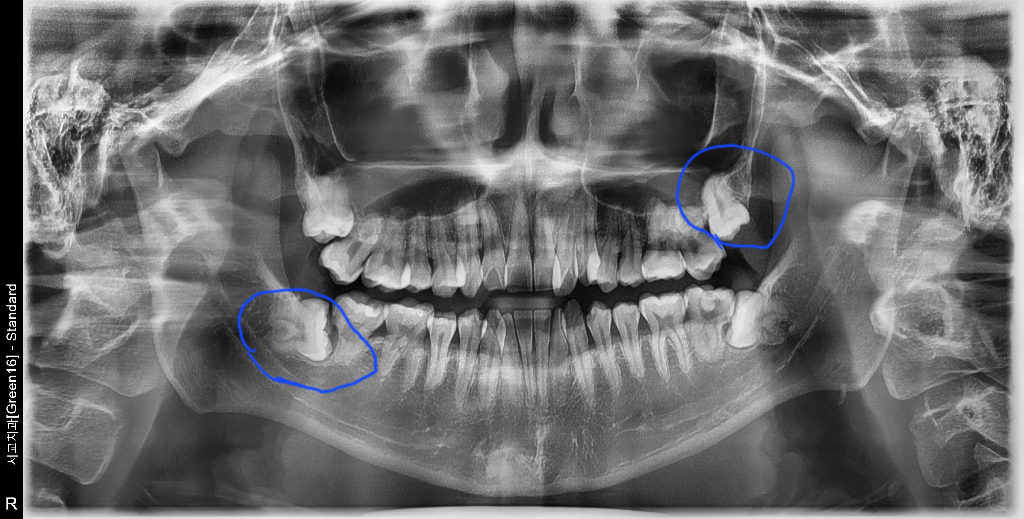

1. 위에 난 사랑니(동그라미) 일반 동네치과에서 뽑아도 되나요?

- 사랑니전문 치과는 아닌데, 위에 똑바로난 사랑니는 신경관 지나가는쪽 아니라 쉽게 뽑을 수 있다하시더라구요. 일반치과에서 뽑아도 될까요?

1, 위의 사랑니가 경사져 매복되어 있으며 특이 오른쪽 위으 사랑니는 고난이도 수술이 필요할 것으로 보입니다. 구강외과 전문의에게 가는 것을 추천합니다. 2. 위의 사랑니도 2-3일간 붓고 아프고 할 것으로 보입니다.